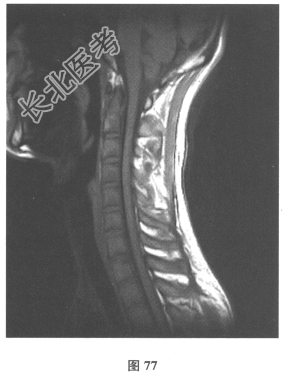

- 简答题3、颅脑MRI:无异常。血清AQP-4抗体(-),脑脊液OB(+),各种自身抗体测定均阴性。VEP:右眼P100潜伏期延长。患者3年前无明显诱因出现双下肢麻木无力,伴有大小便障碍,脊髓MRI显示髓内长T₂信号影,见图76、图77。)此患者的诊断考虑